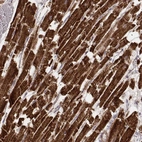

Immunohistochemistry analysis in human heart muscle and liver tissues using AMAb91005 antibody. Corresponding CS RNA-seq data are presented for the same tissues.